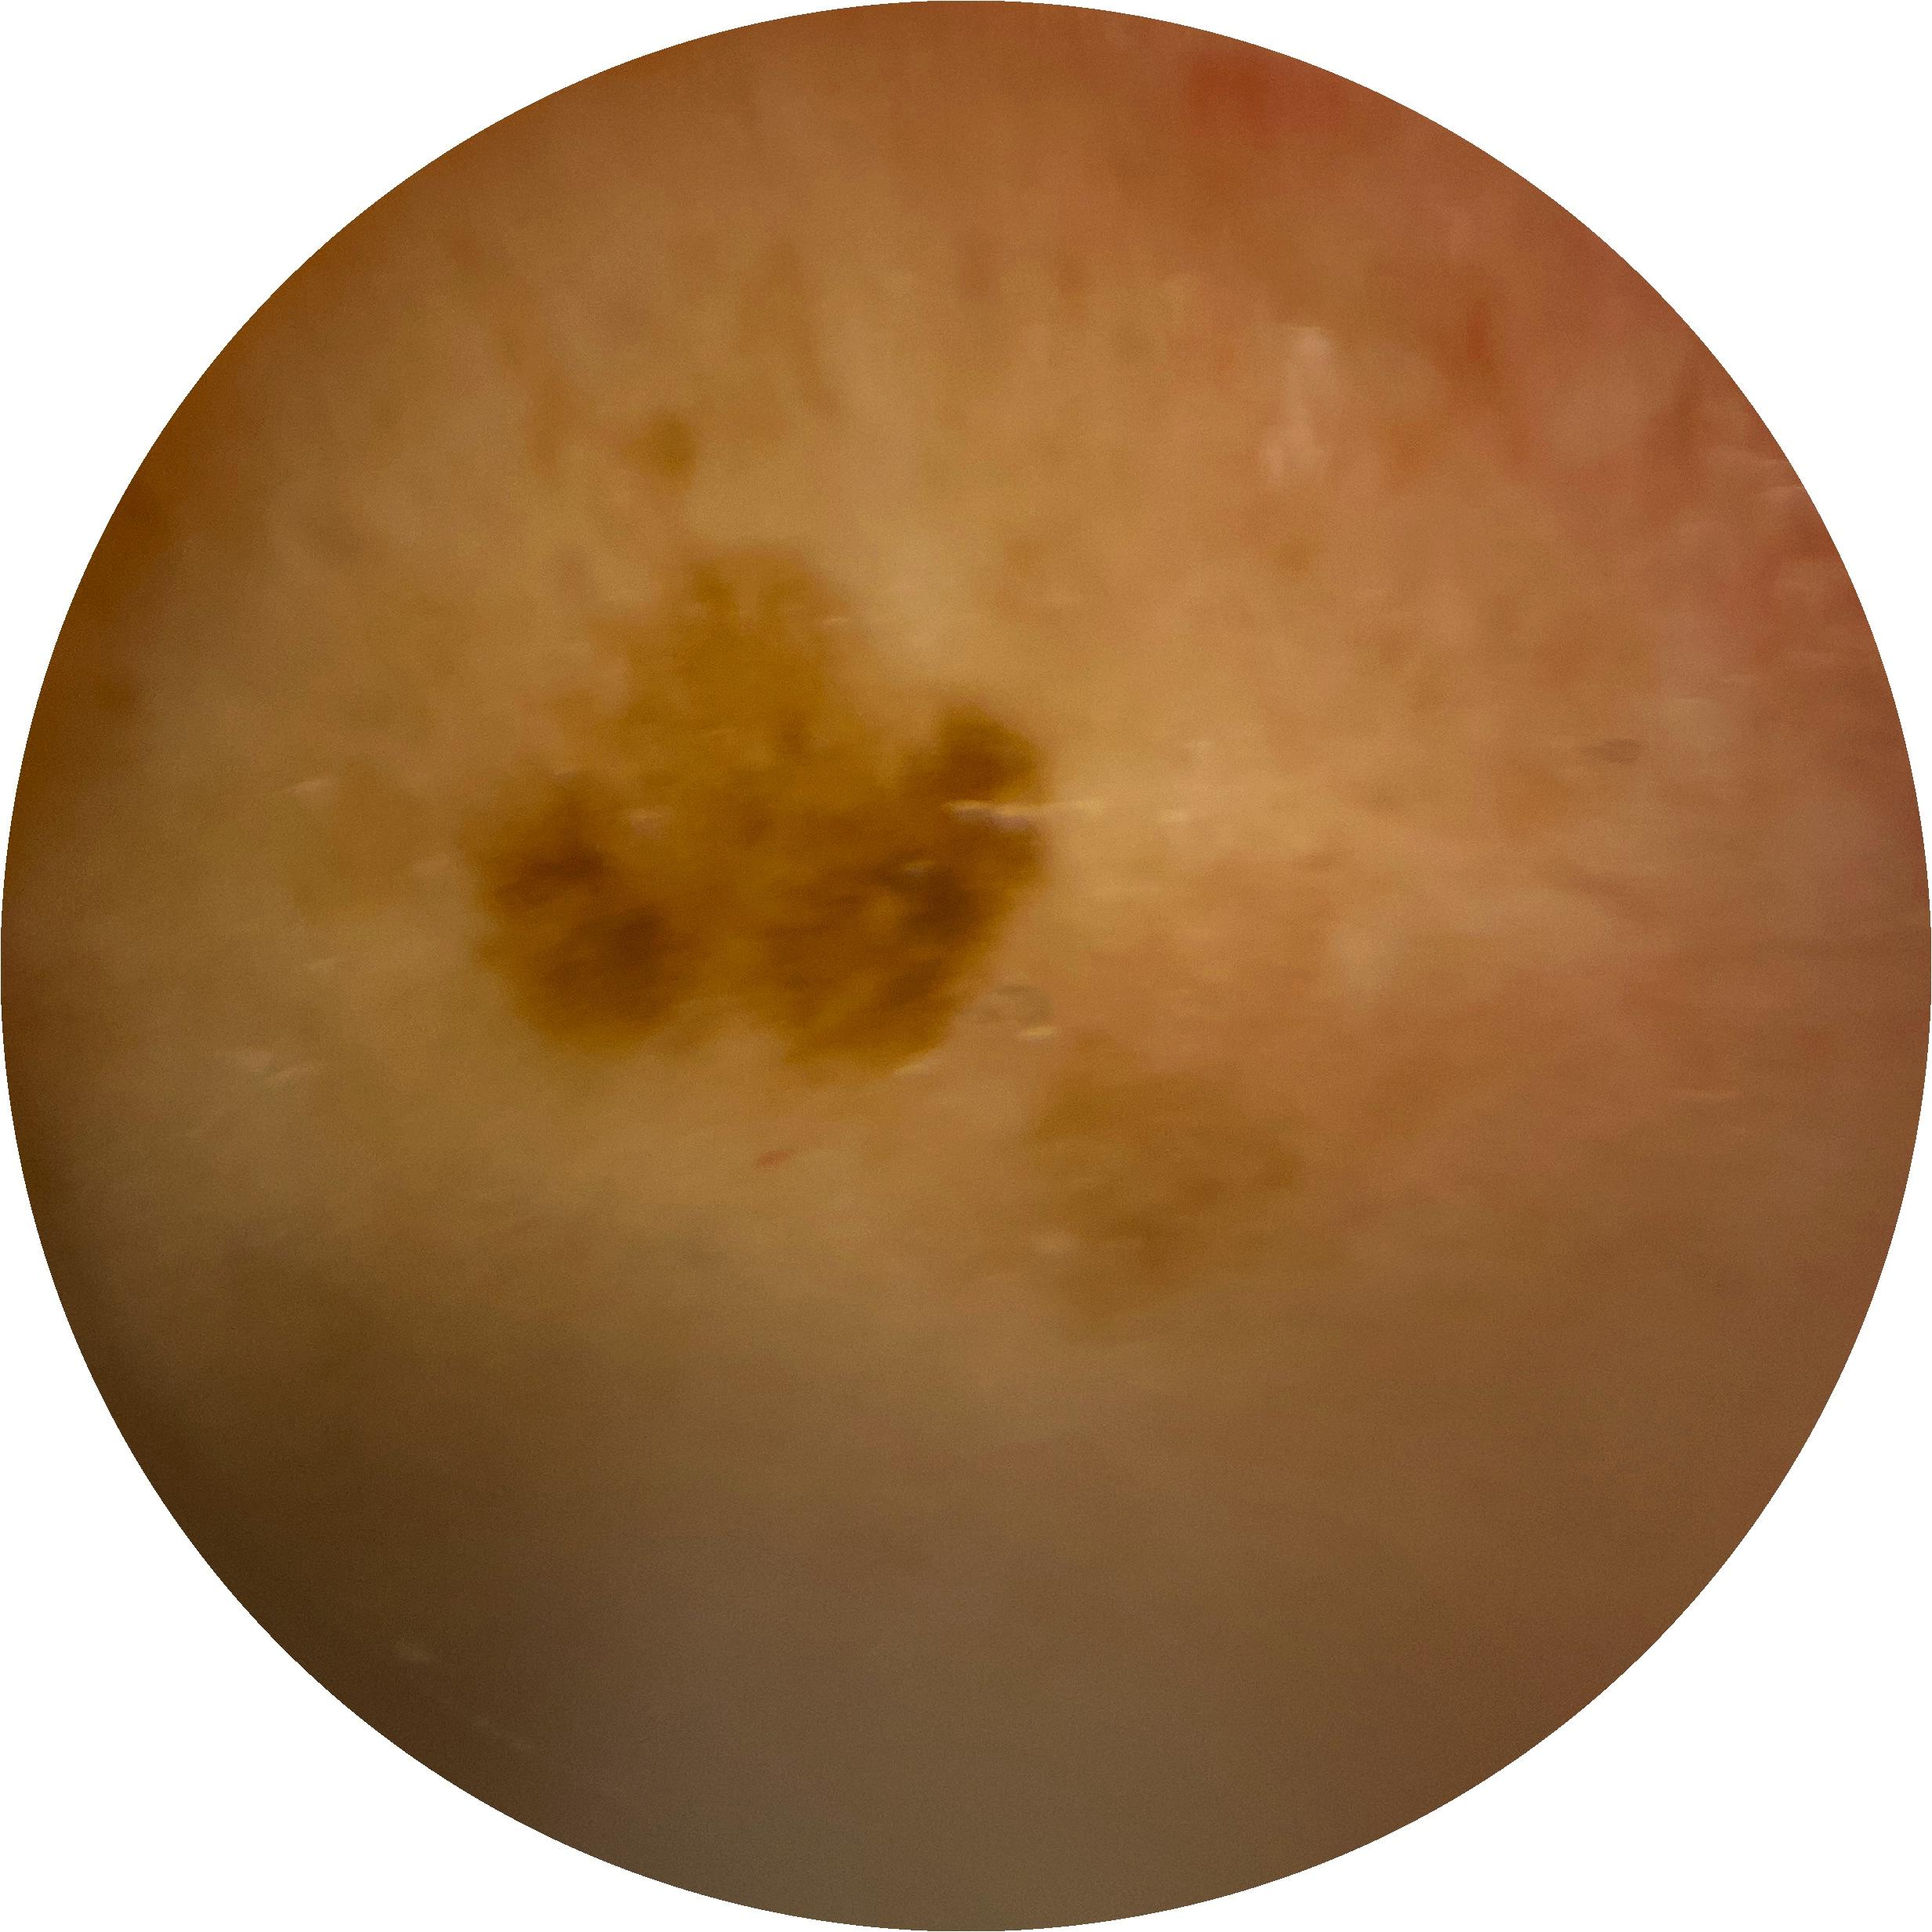

ISIC_4150711

Field Value

acquisition_day 54

age_approx 45

anatom_site_1 Lower extremity

anatom_site_general lower extremity

concomitant_biopsy False

diagnosis_1 Benign

diagnosis_confirm_type single image expert consensus

family_hx_mm True

image_manipulation instrument only

image_type dermoscopic

lesion_id IL_9079054

patient_id IP_8046713

personal_hx_mm True

sex male